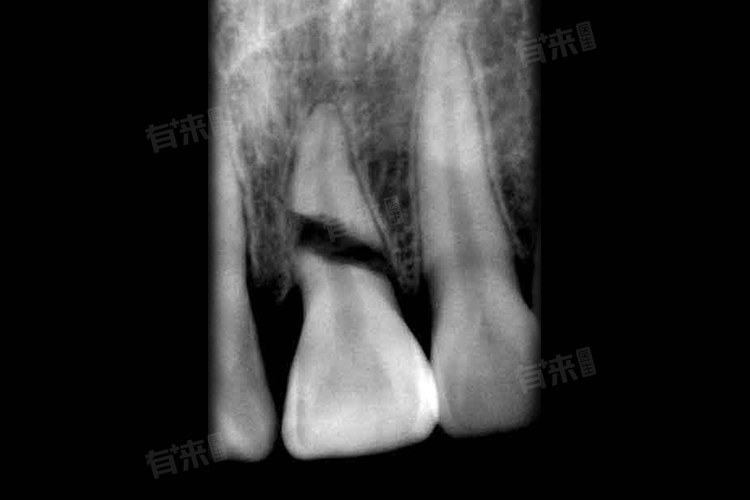

- 通过口腔X光片,能清晰看到牙根断裂位置、程度及方向。若断裂位于牙根尖部,且范围较小,牙齿松动不明显,这种情况相对乐观。但如果断裂靠近牙颈部,或呈纵裂,累及范围大,牙齿松动严重,处理难度则较大。医生还会结合患者症状,如疼痛程度、咬合时的反应等,综合评估牙根断裂情况,为后续治疗提供依据。

- 口腔科:医生通过口腔检查,观察牙齿松动度、牙龈有无出血及肿胀等情况。借助口腔X光片,初步判断牙根断裂位置与程度。若牙根断裂程度较轻,如根尖1/3处断裂且牙齿无明显松动,口腔科医生可能采取固定患牙措施,让其自然愈合,定期复查观察恢复情况。

- 口腔颌面外科:医生通过详细问诊了解受伤原因,结合CT等更精准的影像学检查,全面评估牙根及周围组织状况。若牙根中段或近冠1/3处断裂,且无法通过保守治疗保留牙齿,外科医生会考虑拔除患牙。若牙根断裂伴有牙槽骨骨折,医生会进行手术复位、固定,促进骨折愈合,尽可能保留牙齿。